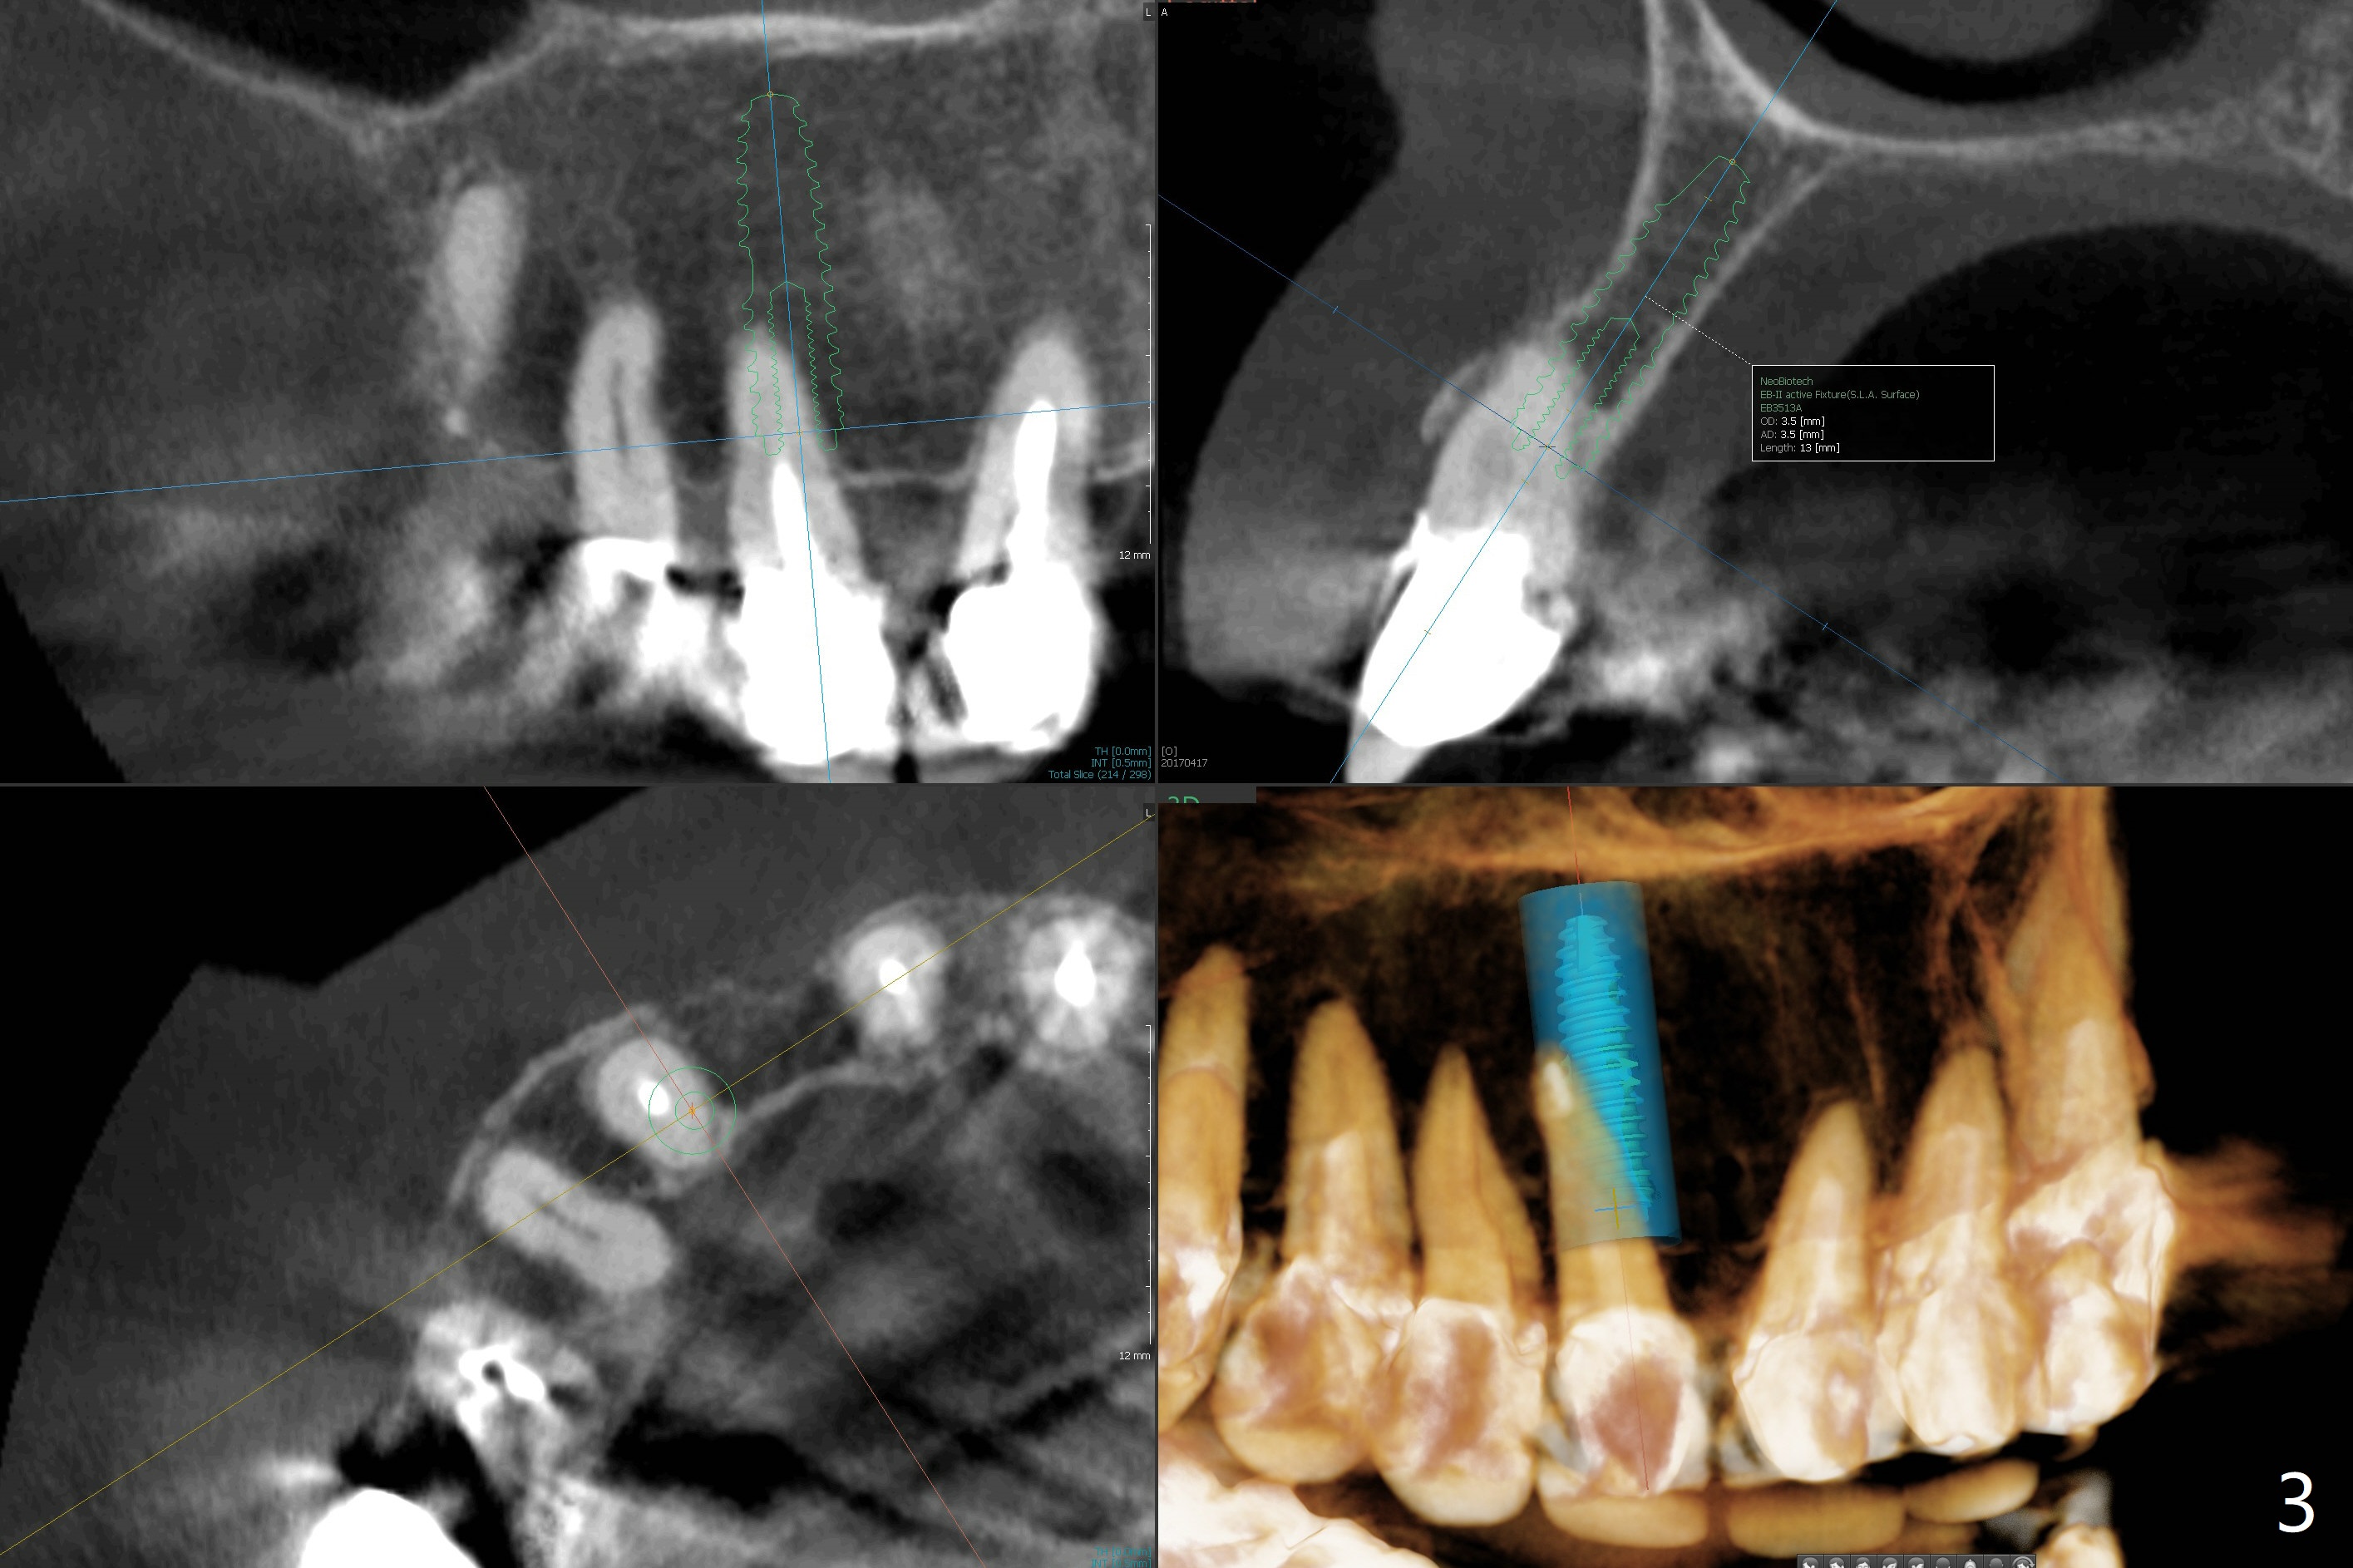

A 67-year-old woman has multiple restoration (difficult for guide preparation). The tooth #6 fractures equigingival with a separated file (Fig.1 <). Because of missing #7, the gingival embrasure between #6 and 8 is large (*). To reduce it, the mesial crest will be trimmed by using 6 mm profile drill after placement of a 3.5x13 mm FC implant (low bone density) and a narrow temporary abutment is going to be used to squeeze the papilla coronally and mesially. In a coronal section, osteotomy will be initiated in the middle of the palatal slope of the socket (Fig.2). A 4 mm x15 degree ~3 mm cuff angled abutment may be used before impression. Take preop photos to show the large gingival embrasure between #6 and 8. The other way to reduce the gingival embrasure is to place an implant mesially. It appears that a 3.5 mm implant is too large for the mesial ridge (Fig.3), while a 2.5 mm one is proper (Fig.4,5).